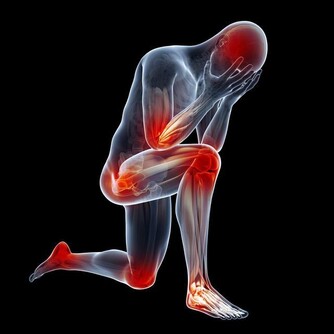

男人的身體健康與自己的前“腺”息息相關,前列腺炎雖然不是什麼大病,但也讓不少男性望而生畏。

事實上,許多生活細節都可能導致疾病發生,比如沒有養成正確的排尿習慣,就可能誘發很多男性疾病。

男性的排尿時間如果明顯變長,而且有滴滴答答、尿不盡的感覺,或者出現尿無力、排尿困難,中老年男性起夜增加等症狀,都要懷疑是否患上前列腺疾病。